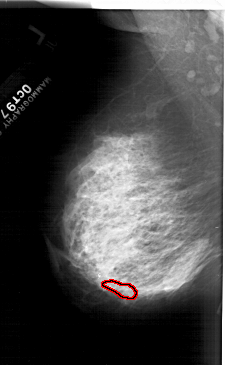

A_1469_1.LEFT_MLO

LEFT_MLO LINES 6556 PIXELS_PER_LINE 4036 BITS_PER_PIXEL 12 RESOLUTION 43.5 OVERLAY

FILE: A_1469_1.LEFT_MLO.OVERLAY

TOTAL_ABNORMALITIES 1

ABNORMALITY 1

LESION_TYPE CALCIFICATION TYPE PLEOMORPHIC DISTRIBUTION LINEAR

ASSESSMENT 4

SUBTLETY 1

PATHOLOGY MALIGNANT

TOTAL_OUTLINES 1

BOUNDARY